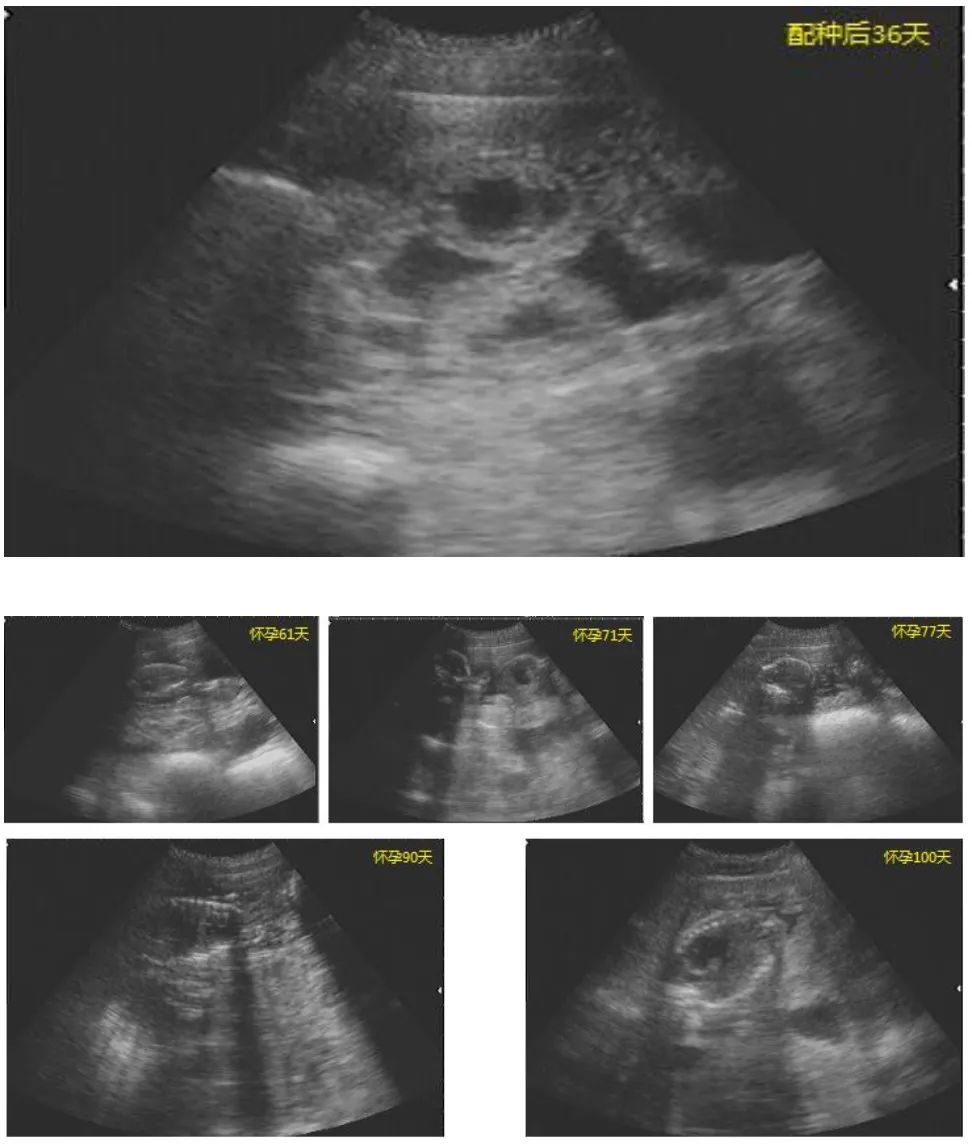

(2)妊娠确认(可选但推荐):配种后第25-30天,用B超复查妊娠,对未孕母猪及时处理,减少饲料浪费。